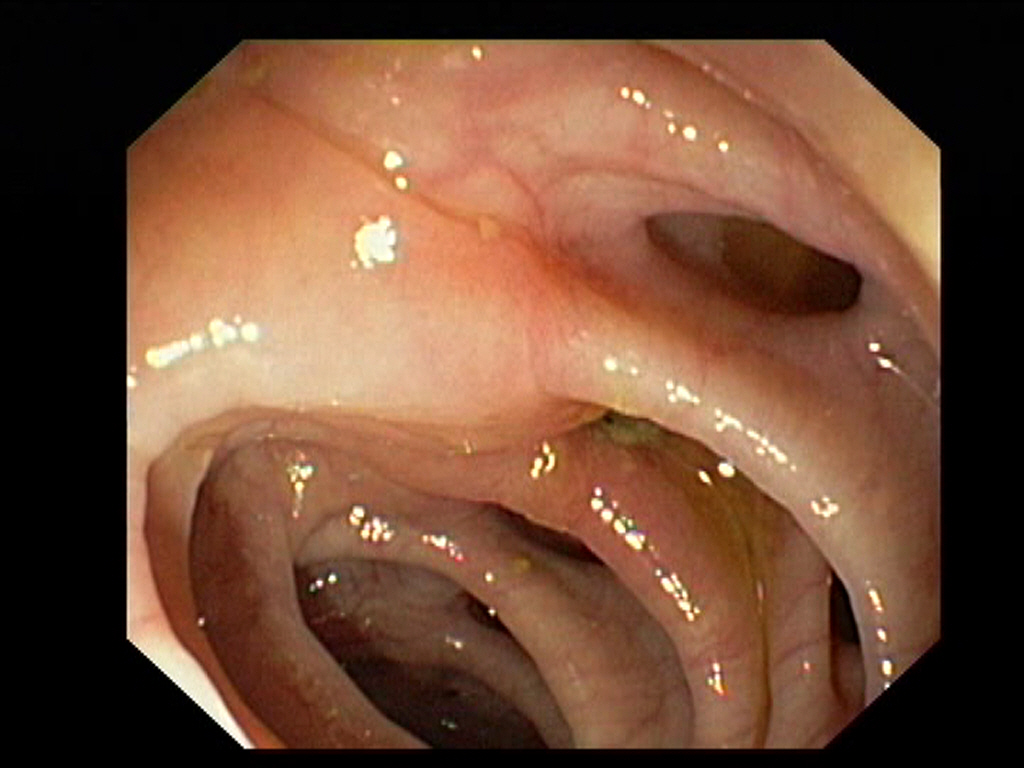

Diverticulosis in the Sigmoid Colon

Diverticulosis in the Sigmoid ColonJust click on a picture!